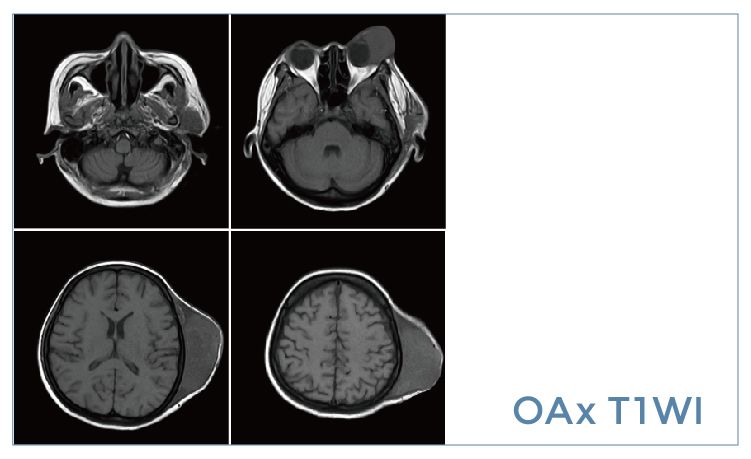

【朗润影像档案】20191101磁共振影像病例结果讨论

【朗润影像档案】磁共振影像病例分享(编号20191101)